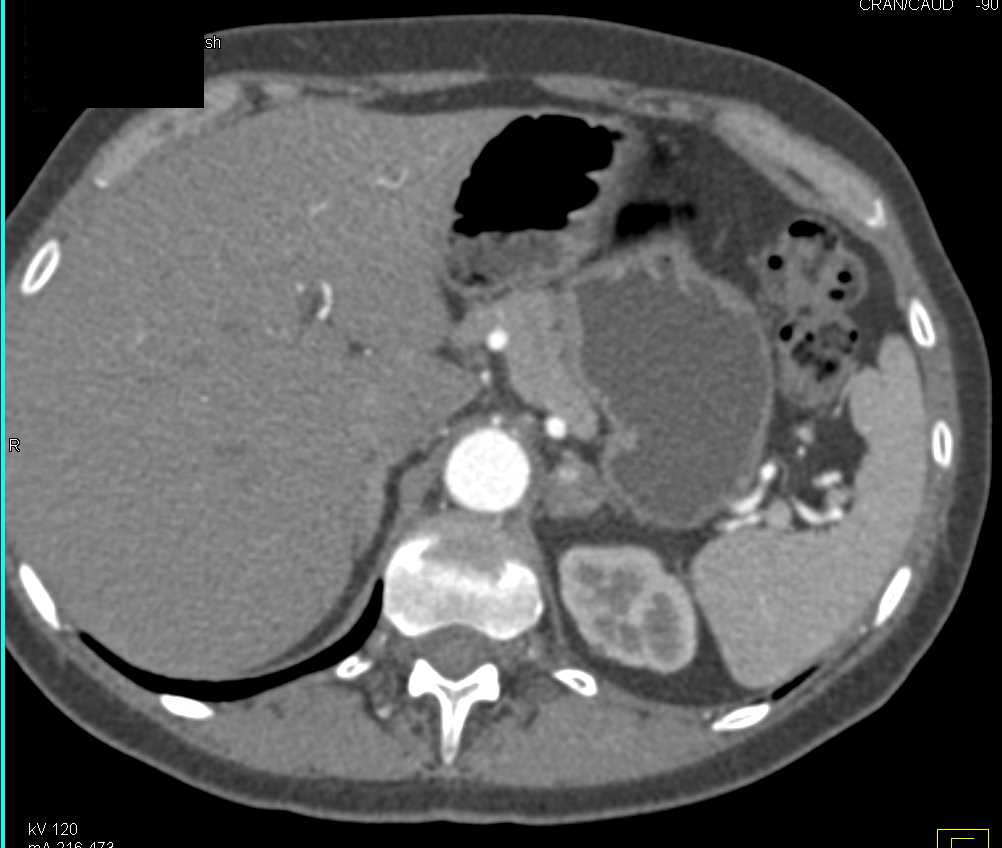

Metastases to the Left Adrenal Gland from Lung Cancer